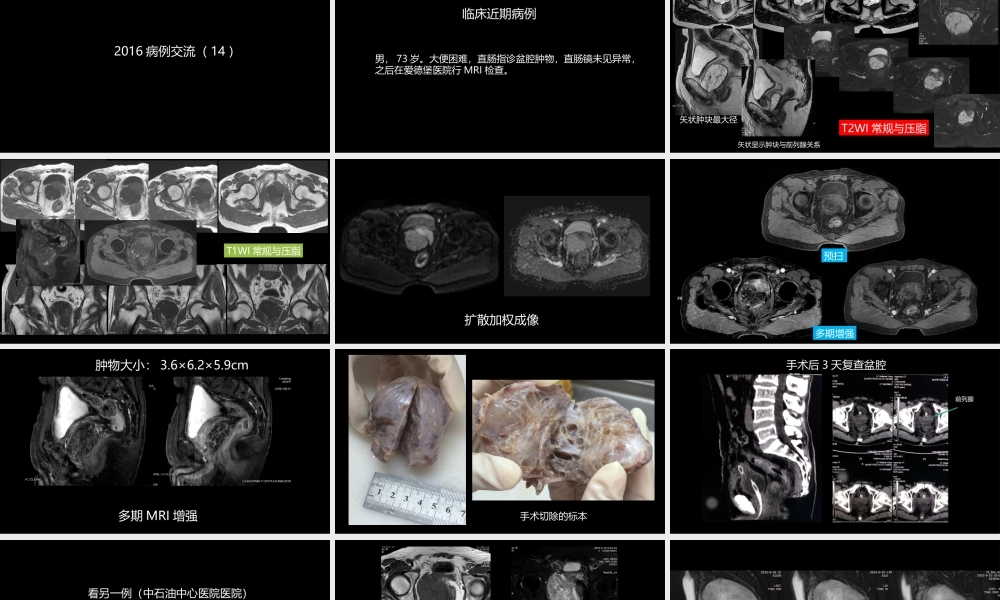

异位前列腺误诊为肿瘤中石油中心医院廊坊爱德堡医院影像科杨景震2016病例交流(14)临床近期病例男,73岁。大便困难,直肠指诊盆腔肿物,直肠镜未见异常,之后在爱德堡医院行MRI检查。T2WI常规与压脂矢状肿块最大径矢状显示肿块与前列腺关系T1WI常规与压脂扩散加权成像预扫多期增强多期MRI增强肿物大小:3.6×6.2×5.9cm手术切除的标本手术后3天复查盆腔CT前列腺看另一例(中石油中心医院医院)男,61岁。以排尿浑浊就诊,尿检及PSA未见异常,超声检查发现前列腺肿物,行MRI检查。T1WIT2WI矢状T2WI:肿块内血管流空征扩散图ADC图扩散加权成像预扫动脉早期动脉后期期静脉期静脉后期MR多期增强第一例诊断什么?术前MRI诊断:侵袭性血管粘液瘤或肌纤维母细胞瘤手术:探查手术口较小,暴露并分离肿物后顺利切除之,术中有较多的出血。肿物切开,可见大量粘液。(爱德堡医院、中石油中心医院病理科)病理:肿物内纤维组织间可见前列腺腺体,区域腺体萎缩并扩张,腔内可见前列腺石,形态符合前列腺良性病变,结合影像表现及手术所见首先考虑异位前列腺(慢性炎性及变性)。致谢:中科院肿瘤医院病理科张宏图教授病理读片指导病理图病理图病理图前列腺异位:极其罕见,最早在1894年报道,之后相继有个案,可以异位于盆腔、尿道、精囊、阴囊、附睾。而作为单独的较大盆腔肿块形式并误诊为肿瘤,这种形式在中、西文检索未见到报告。承德医学院学报2013年及河北医药1981年分别报道1例异位的前列腺位于附睾、阴囊(黄豆大小)的病例;2004年临床泌尿外科杂志、云南医药各有1例前列腺组织异位于膀胱的个案。或误诊为膀胱息肉或误诊为前列腺增生。通过我们这例异位的前列腺肿块诊断和治疗过程表明,影像学特别是MRI检查的多序列应用虽然有一定的帮助,仍需要依赖于病理学的认定。尤其是异位的前列腺发生退变或炎性变时,影像学表现不宜与肿瘤区分。本例的MRI所见富水成分并结合大体标本,尚不能除外源自异位前列腺之囊腺瘤可能。Prostatecancerarisinginectopicprostatictissuewithintheleftseminalvesicle:ararecasediagnosedwithmulti-parametricmagneticresonanceimagingandmagneticresonanceimaging-transrectalultrasoundfusionbiopsy.BMCMedImaging.2016Feb24外院手术及病理诊断:侵袭性血管粘液瘤MRI诊断:盆腔肿物,考虑起自会阴部1、血管肌纤维母细胞瘤(AMFB)2、侵袭性血管粘液瘤(AAM)第二例侵袭性血管粘液瘤,温和的梭形细胞及星形细胞均匀地分布...